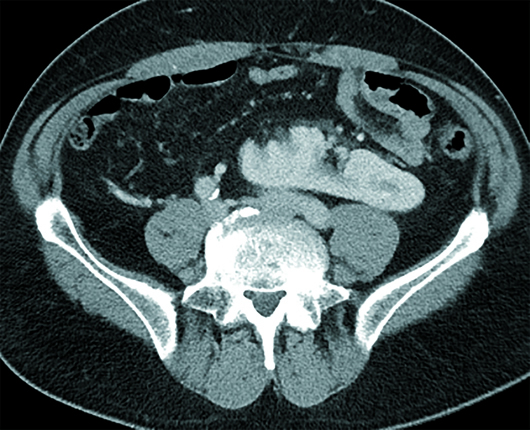

Axial, sagittal, and coronal contrast-enhanced CT images of the abdomen and pelvis revealed a 5 mm ureterolith at the right ureterovesicular junction (not shown), with mild right hydroureteronephrosis (Figures 1 and 2). The right and left kidneys were fused to the left of the abdominal midline, with separate collecting systems and ureters (Figures 3, 4, and 5). The left renal moiety cortex, hila, and collecting system were oriented normally without hydroureteronephrosis (Figure 6). The crossed, fused right renal moiety was oriented craniocaudally and medially in the coronal plane in reference to the left moiety (Figure 4). Moreover, the crossed right renal moiety is malrotated with an inferolaterally oriented hilum, consistent with sigmoid configuration (Figure 4).

Figure 4